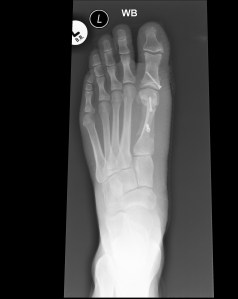

Well I made it back to London this week and back to work on Monday. The foot is on the mend and I have now progressed to the B3 Cbt Engr post final exercise hobble! All of my x-rays have now come back fine and I am now encouraged to walk but it is still a bit uncomfortable. It takes me twice as long to get to work as I have to walk slowly to the bus stop and site office but hopefully it will be back to whacky races on the bike again soon.  At least my foot looks like a good bit of engineering now with it’s 3 titanium bolts!LF DP postop 01-04